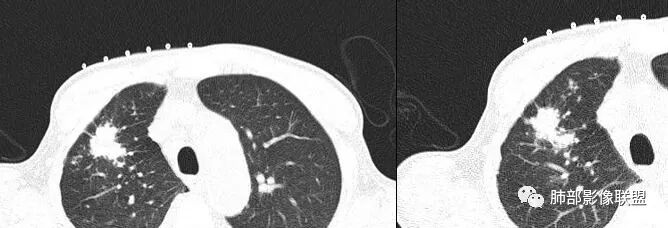

但是呢,我觉得这个病灶,它确实有一些恶性的特点,边缘膨隆,深分叶,有深短毛刺。

感觉胸膜上有很多结节,层面不够,还有一点胸水。

2.右肺上叶斑片影、结节影、硬树丫,密度均匀未见钙化或液化。近胸壁处见分叶结节影及棘状突起,胸膜牵拉凹陷。

3.近胸壁处边缘分叶结节影,胸膜凹陷等使人怀疑基础疾病上出现新生物的可能性。

4.细看病灶有些散,有堆砌感。注意结核灶也常有胸膜牵拉。